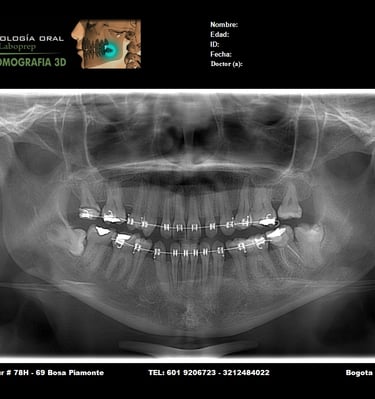

Galería

Imágenes de nuestros servicios radiológicos.